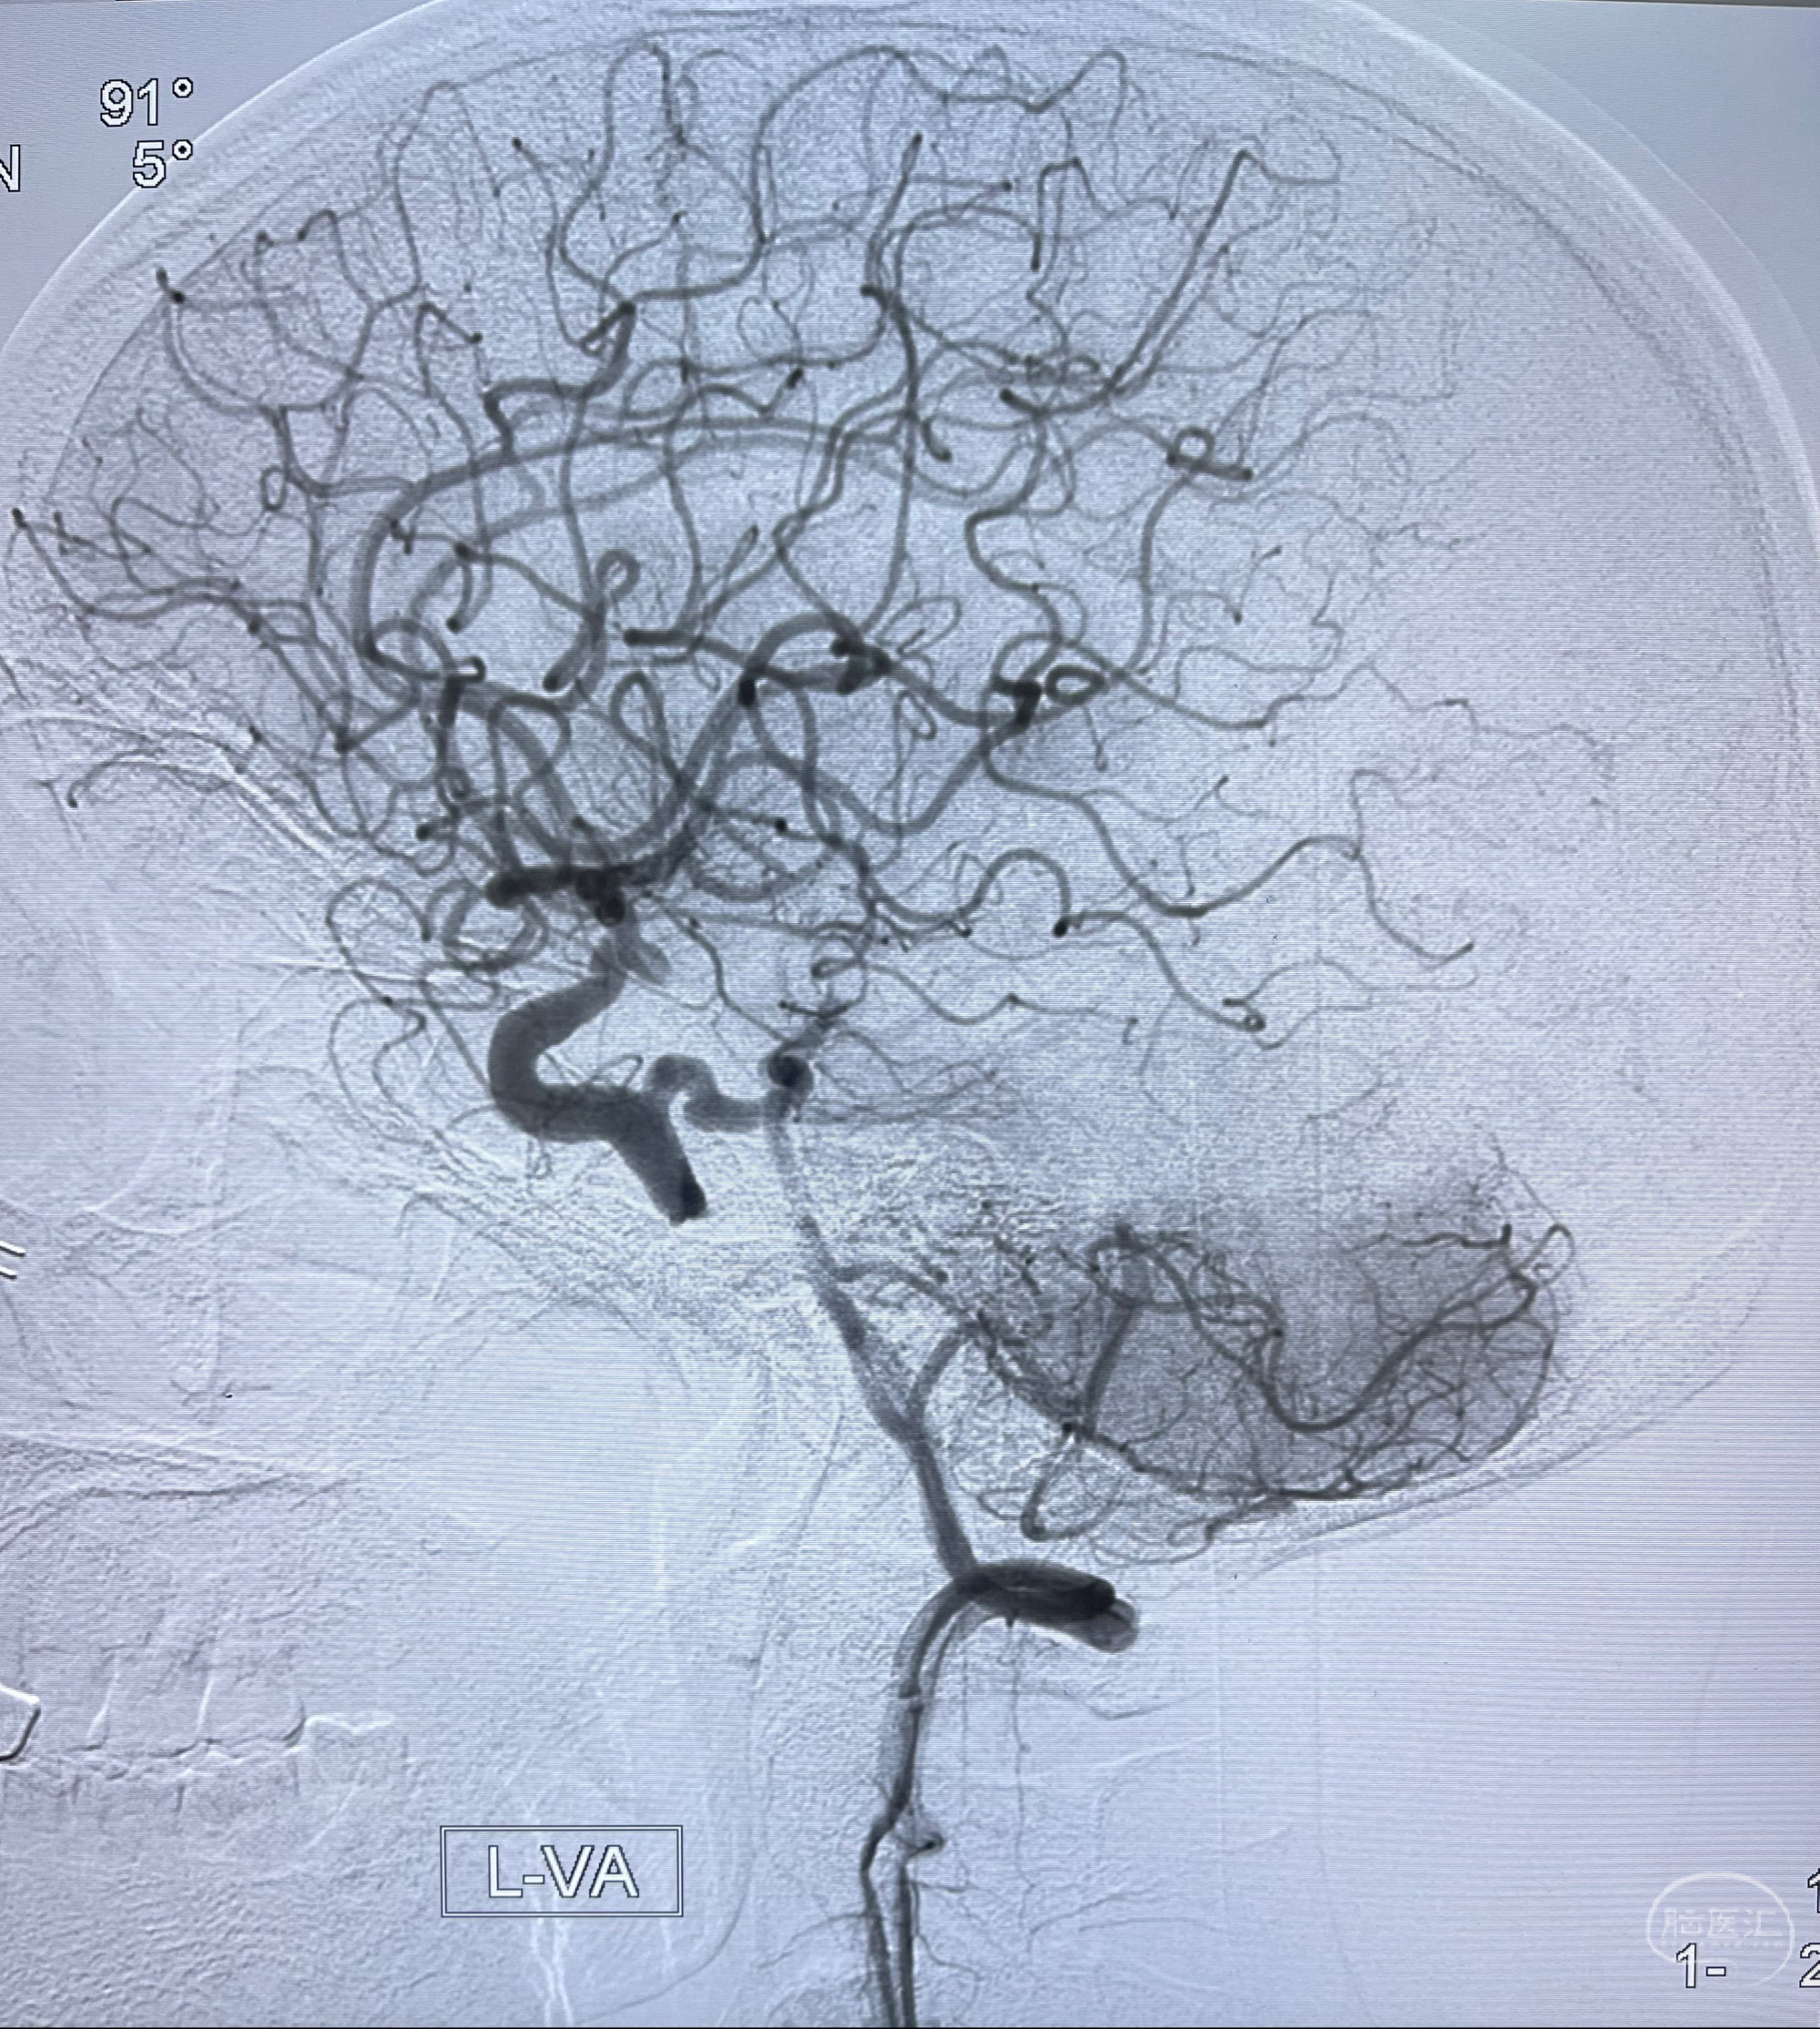

脑血管造影2023.03.06:右侧颈内动脉颈段至岩骨段闭塞,可见后后循环通过原始三叉动脉吻合代偿至海绵窦段,后交通区可见囊状造影剂填充影,左侧锁骨下动脉呈“残端”改变,呈“右侧颈总动脉支架成形术后改变”,支架内血流通畅,可见后交通吻合显影至左侧大脑后动脉,并可见左枕动脉吻合椎动脉至锁骨下动脉

2.右侧颈内动脉由后循环经右侧后交通动脉前向代偿显示

3.右侧颈内动脉眼动脉段近后交通动脉处重度狭窄伴前壁不规则动脉瘤

1.箭头处为右侧颈内动脉后交通动脉处重度狭窄,狭窄前壁为不规则动脉瘤;

2.狭窄远端颈内动脉由左侧颈内动脉经左侧后交通动脉—基底动脉顶—右侧后交通—右侧颈内动脉—右侧大脑中动脉途径代偿

左侧颈内动脉经左侧后交通动脉—基底动脉顶—右侧后交通—右侧颈内动脉—右侧大脑中动脉途径代偿